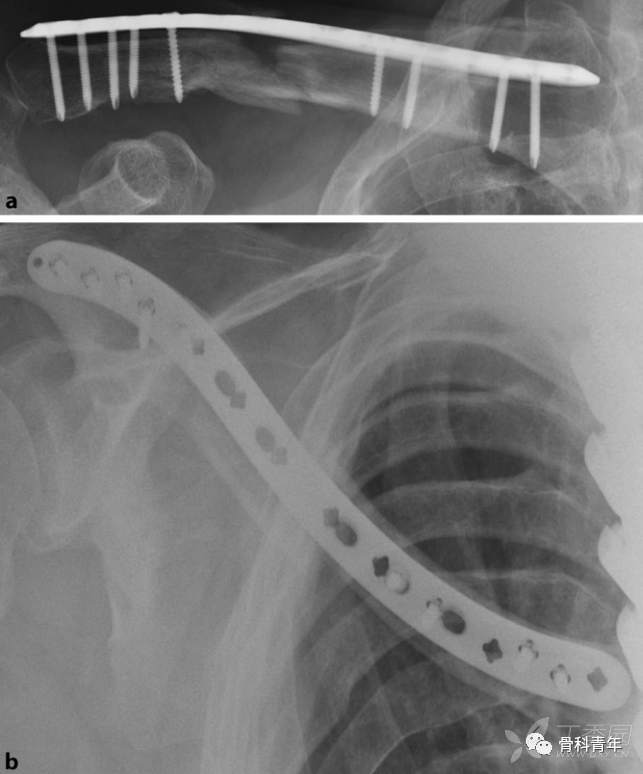

本例演示患者为锁骨中段粉碎性骨折,预估钢板需要防止的位置及长度,在锁骨内外侧缘分别作一2-3cm切口。

通过两边切口,骨膜剥离子建立骨面隧道,插入钢板,远近端夹持复位或采用Joystick技术复位,复位后先经钢板最外侧孔置入克氏针或皮质螺钉临时固定,复位满意后经钢板内侧孔置入克氏针固定。

在临时固定复位满意后,经钢板远近端最靠近骨折块的钉孔,置入一枚皮钉。如此时骨折块存在成角或移位,可经复位钳夹持复位。复位后两边钉孔依次置入锁定螺钉桥接固定。